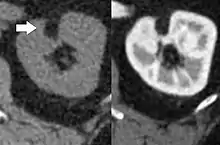

Three methods of scanning can detect Angiomyolipomas: ultrasound, computed tomography (CT), and magnetic resonance imaging (MRI).[5] Ultrasound is standard and is particularly sensitive to the fat in Angiomyolipomas, but less so to the solid components. However, accurate measurements are hard to make with ultrasound, particularly if the Angiomyolipoma is near the surface of the kidney (grade III).[4] CT is very detailed and fast, and allows accurate measurement. However, it exposes the patient to radiation and the dangers that a contrast dye used to aid the scanning may itself harm the kidneys. MRI is safer than CT, but many patients (particularly those with the learning difficulties or behavioural problems found in tuberous sclerosis) require sedation or general anaesthesia, and the scan cannot be performed quickly.[3] Some other kidney tumours contain fat, so the presence of fat is not diagnostic. Distinguishing a fat-poor angiomyolipoma from a renal cell carcinoma (RCC) can be difficult.[6] Both minimal fat AMLs and 80% of the clear-cell type of RCCs display signal drop on an out-of-phase MRI sequence compared to in-phase.[7] Thus, a lesion growing at greater than 5 mm per year may warrant a biopsy for diagnosis.[3]